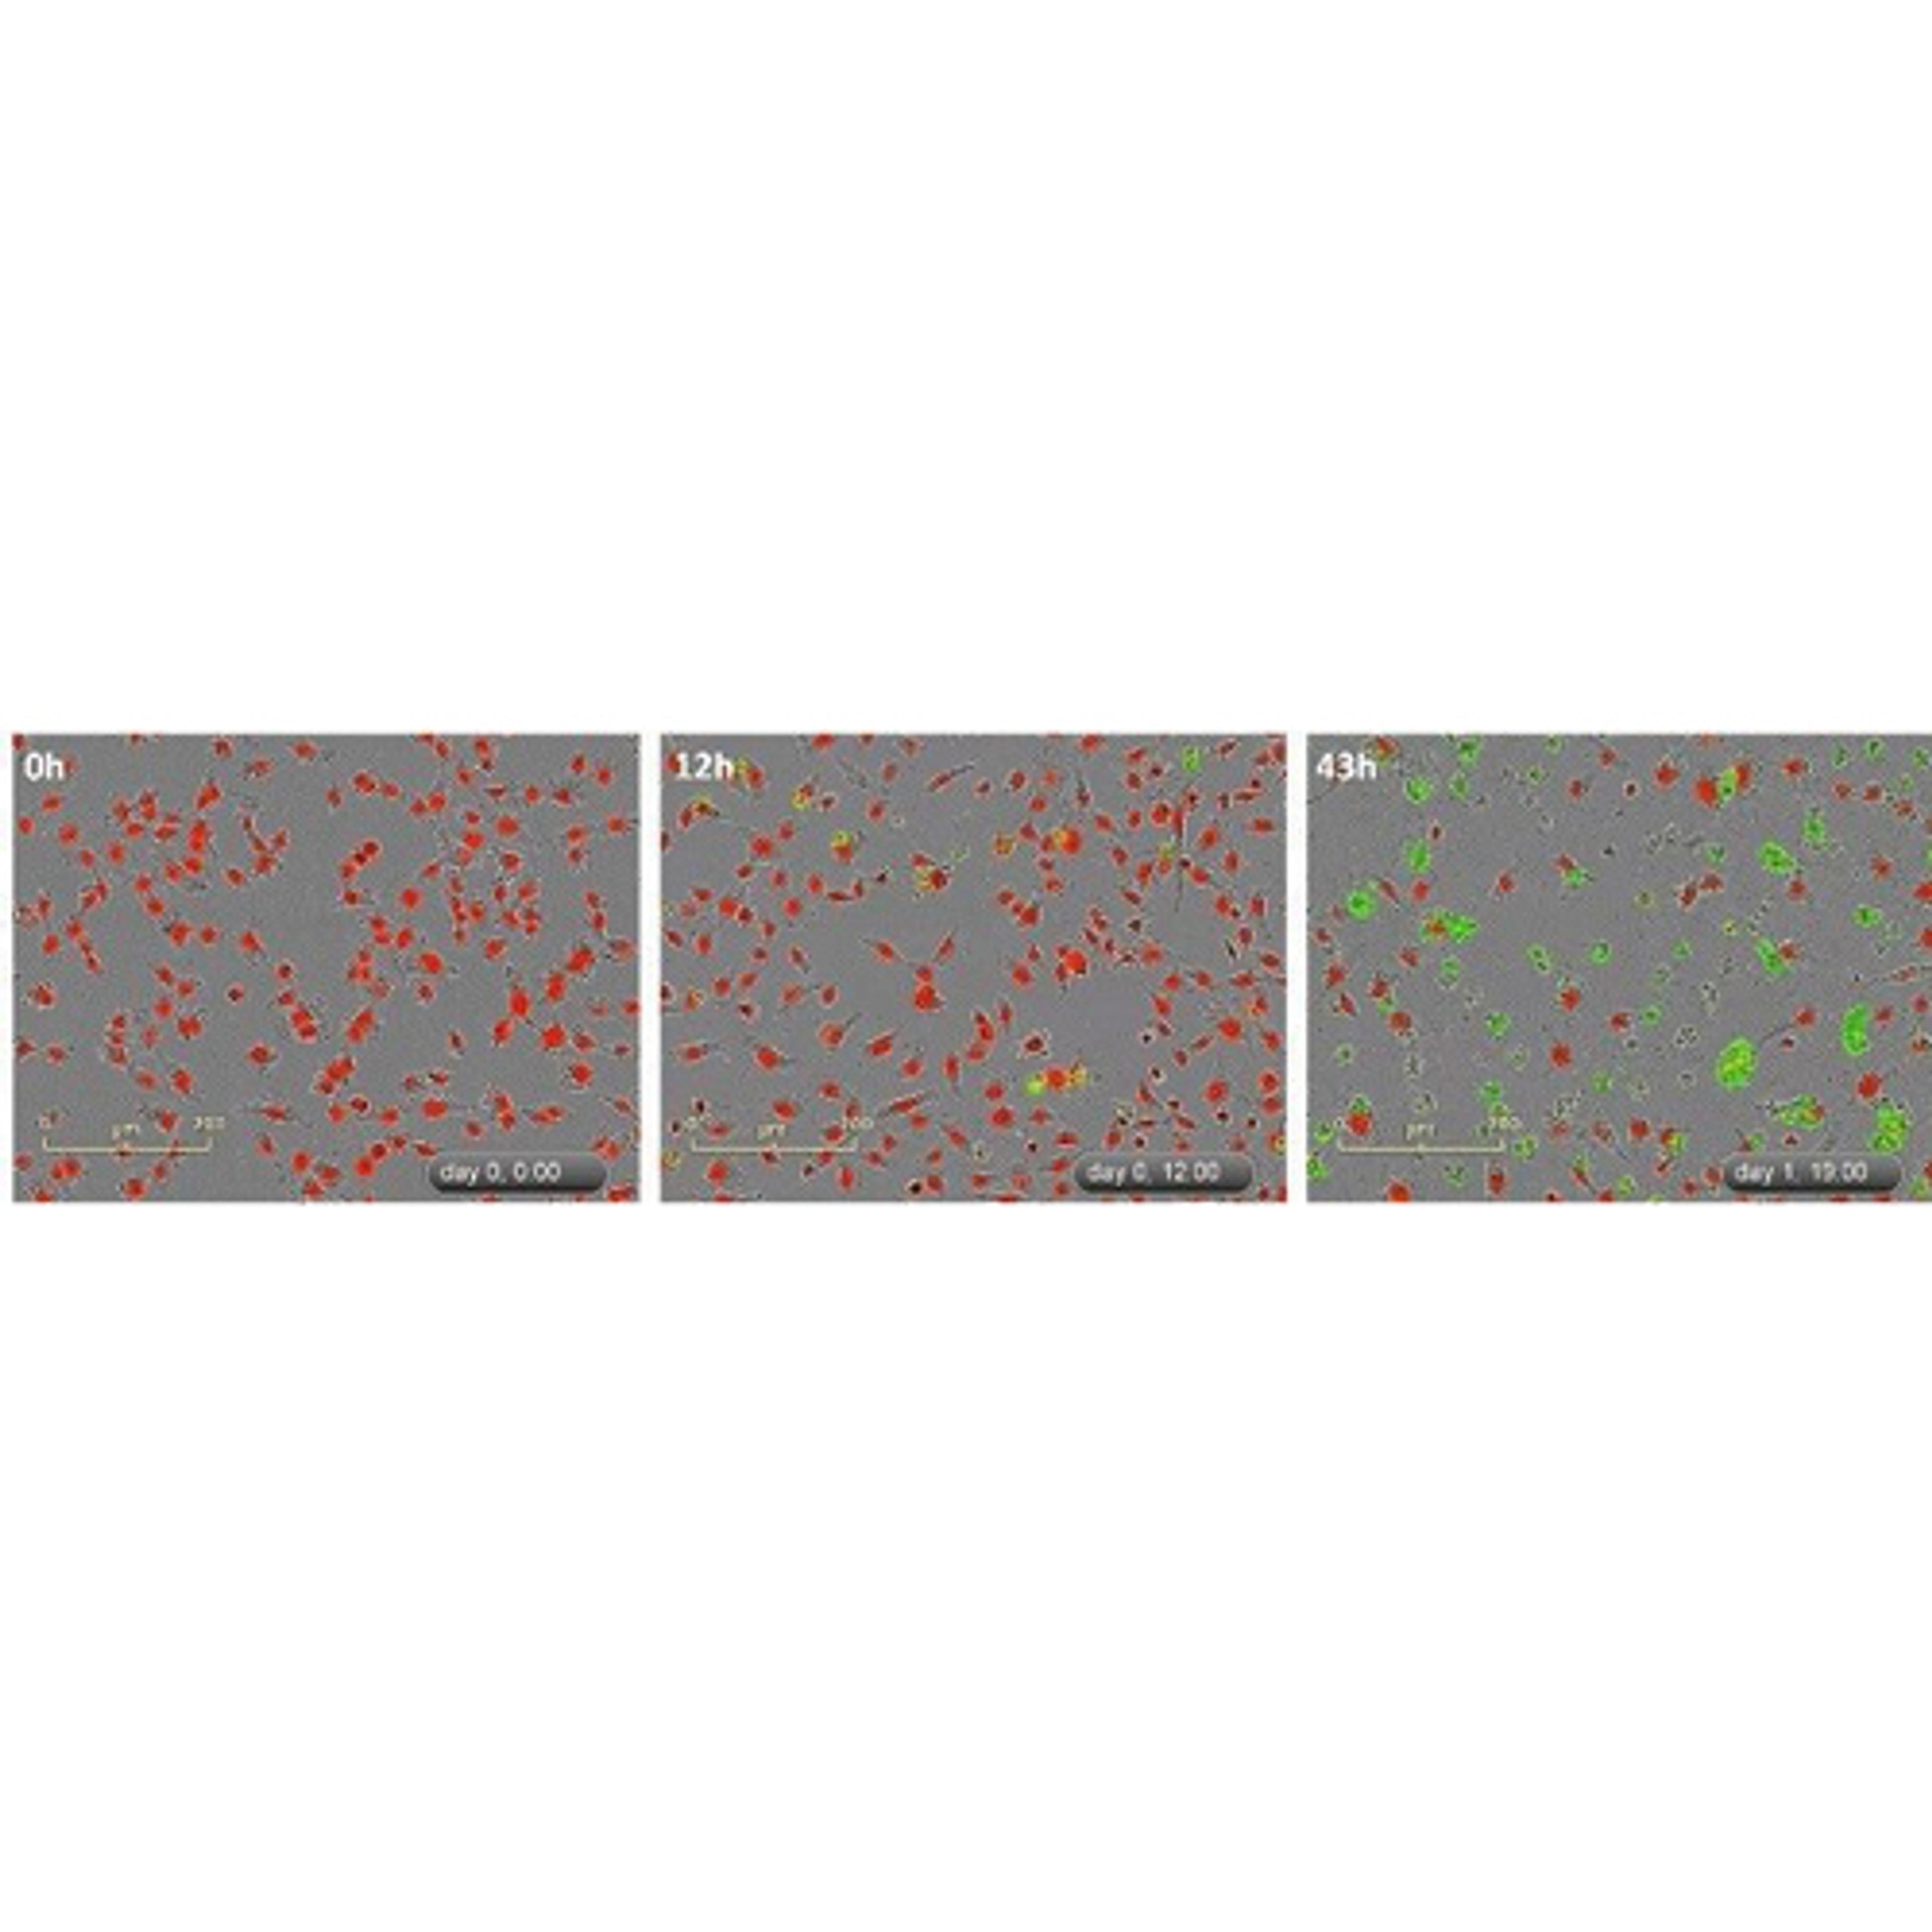

As a cancer researcher focused on developing and optimizing drug therapies, the Incucyte has revolutionized the way I track cancer cell behavior, assess drug efficacy, and uncover new therapeutic candidates. Traditional endpoint assays provide only static snapshots of cellular responses, often missing critical dynamic changes. The Incucyte overcomes this limitation by enabling real-time, continuous imaging of live cells, allowing for kinetic analysis of drug effects over days or even weeks. The system’s ability to capture both phase-contrast and fluorescence imaging in a label-free or labeled manner has been particularly valuable in monitoring cancer cell proliferation, apoptosis, and migration. I can now directly observe how drug-treated cells respond over time, rather than relying solely on indirect biochemical assays. This has been crucial in identifying dose-dependent responses, resistance mechanisms, and combination therapy synergies with unprecedented precision. Moreover, the automated data analysis tools streamline quantification, reducing variability and increasing reproducibility across experiments. With its non-invasive imaging approach, I can test multiple conditions simultaneously, improving throughput and accelerating drug discovery. The Incucyte has fundamentally changed how I conduct cancer drug research, providing deeper insights into treatment efficacy and enabling faster, more informed decisions in the development of novel cancer therapies.

Change can happen in an instant. Whether simply assaying cell health or more complex processes like migration, invasion, or immune cell killing, see what your cells are doing and when they do it. Incucyte® instruments, proprietary assays and reagents provide you with the ability to gain new insights into biological processes via real-time, quantitative analysis of live cells.

Conventional approaches to cell analysis only capture a single time point, enabling only single-point and end-point measurements, and cells are perturbed or destroyed as part of the assay process. Incucyte® systems offer the advantage of performing live-cell analysis without ever having to displace cells or disrupt their surroundings. The system automatically and continually collects and analyzes images throughout the course of an experiment while cells remain unperturbed in a physiologically relevant environment. Furthermore, Incucyte® accommodates multiple users and applications seamlessly and combines information-rich, image-based analysis with the convenience and throughput of microplate assays.

- Monitor metabolism in cancer cells

- Complex immune-tumor cell interactions

- Apoptosis (caspase 3/7 for live-cell imaging)

- Cytotoxicity

- Immune response – Immune cell killing